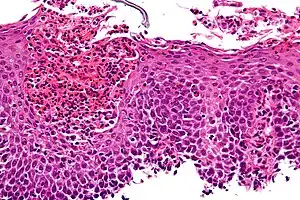

O diagnóstico se baseia nos sintomas e nas biópsias do esôfago, que são obtidas através de endoscopia digestiva alta. As amostras obtidas pelas biópsias devem ser examinadas por um patologista, que faz o diagnóstico de esofagite eosinofílica quando encontra mais de 15 eosinófilos em campo de grande aumento.